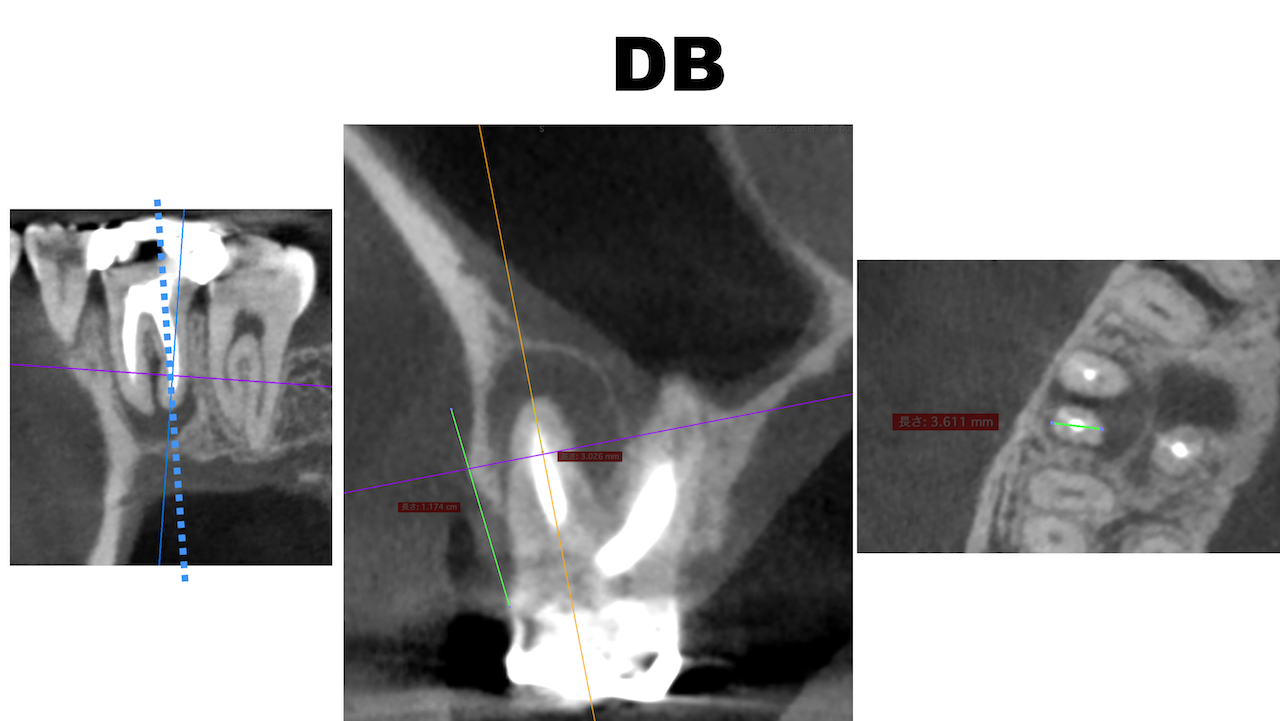

この流れで計測すると以下のようになる。

#3 DB

MBとDBは近接し、3mmで切断した際の頬舌的な厚みも3.5~4mmだ。

そしてMB1, MB2は近接している。

またMBもDBも近接している。

以上のことからこのApicoectomyは容易であると私にはわかる。